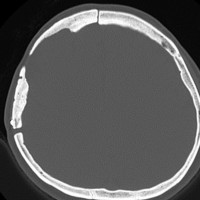

骨内髄膜腫 osseous meningioma

骨内増殖をする髄膜腫です。頭蓋骨腫瘍と間違えるようなものです。触った感じは骨腫ですが,CTでは,表面が毛羽立っていて,頭蓋冠に浸潤していることが特徴です。浅側頭動脈からの豊富な血流があります。

わずかですが頭蓋内にも腫瘍があり,硬膜が肥厚してガドリニウム増強されます。

頭蓋骨をかなり広範におかすので骨は捨てません。開頭して取り外した骨の厚くなっている部分と髄膜腫で軟らかくなっている部分を削除して,それから骨片をオートクレーブで短時間熱処理して,元あった所にもどします。下の画像は手術後1年半が経過したものですが,髄膜腫の再発はなく,熱処理骨弁は吸収されないで生着しています。